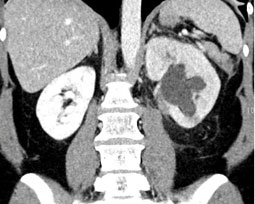

Beim sich anschliessenden Ultraschall der Nieren zeigt sich der Aufstau des Urins in der Niere. Bei unklarem Befund erfolgt noch eine Computertomografie. Mit ihr können weitere Erkrankungen oder sogenannte komplizierende Faktoren (Nierensteine, Eiterhöhlen) ausgeschlossen werden.

![]() |

| Ultraschallbild einer Nierenbeckenabgangsenge | Computertomografie der Nierenbeckenabgangsenge |